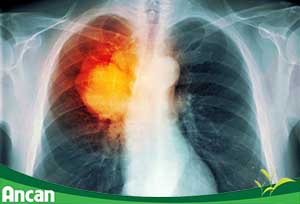

Tại sao ung thư phổi lại nguy hiểm nhất trong các loại ung thư?

Hiện nay, ung thư phổi đang được xếp vào loại ung thư nguy hiểm nhất, có tỷ lệ mắc bệnh cũng như tỷ lệ tử vong cao nhất trong các loại ung thư. Nguy hiểm hơn, các yếu tố nguy cơ gây nên căn bệnh này đang ngày càng gia tăng trong cuộc sống hàng ngày của chúng ta.